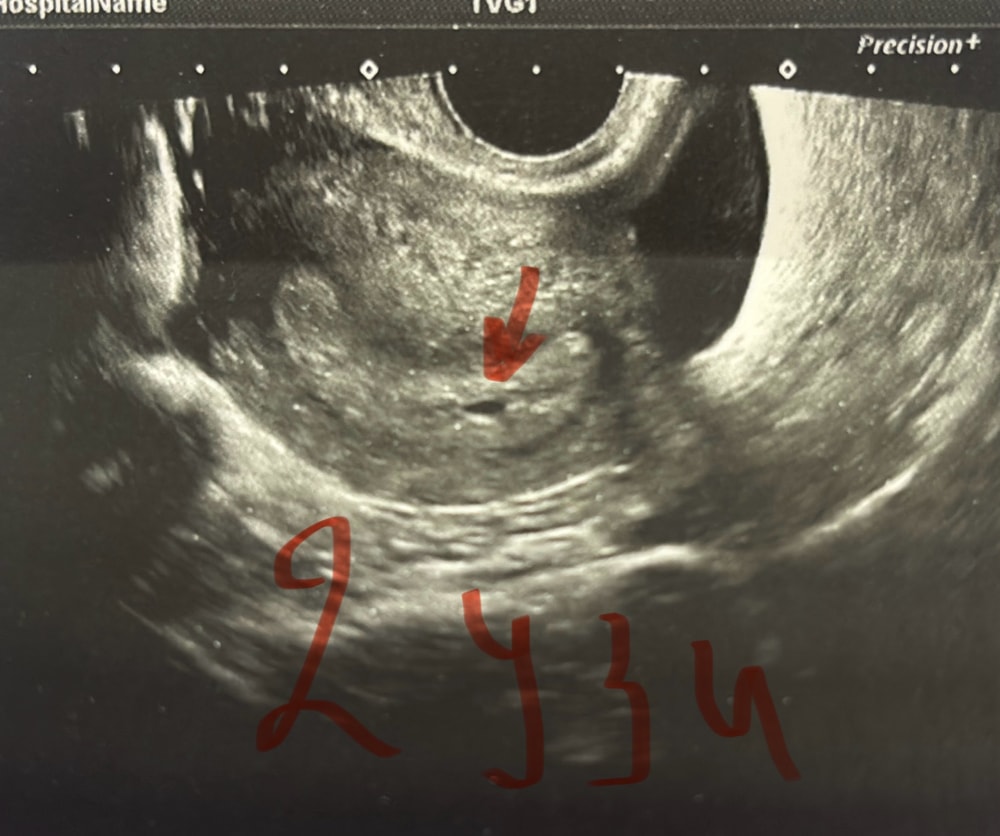

УЗИ пя 4 мм

Обследования, узи, анализыДевочки, всем привет 👋 может было у кого так, у меня акушерский срок 5 недель 4 дня. по узи (на 33 день от начала месячных) маленькая точечка где-то 1 мм ( поставили под вопросом маточную беременность )Хгч на 37 день 171,. Была на узи сегодня (40 день) пя 4,03 мм , и жт в левом яичнике 17мм. Говорит, ждем, чтобы малышарик набирался сил и мы его наконец-то увидели. Пугает, что она говорит, что странно всё на таком сроке, маленькое пя. Но цикл у меня всегда был не регулярный (СПЯК) , поэтому я даже не могу сказать, сколько у меня задержка и когда была О. Может было так у кого, поделитесь своей историей, а то я что-то переживаю после слов врача